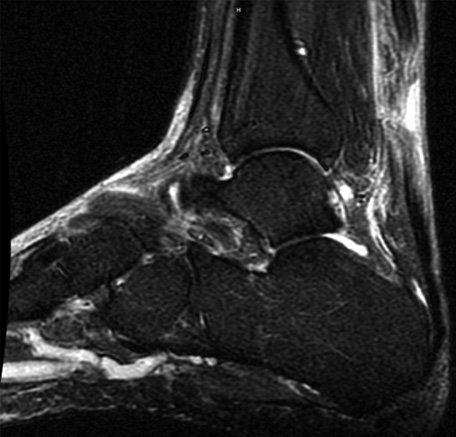

Ankle MRI demonstrating a midsubstance Achilles rupture with a 2 cm gap

Courtesy of Nigel Hsu, MD